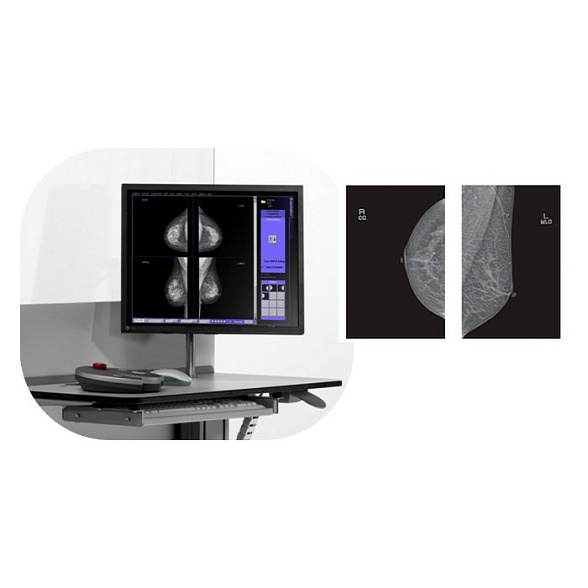

Маммограф Pinkview-RT аналоговый Bemems

Аналоговый маммограф Pinkview-RT (Bemems)

Аналоговый маммограф Pinkview-RT от компании Bemems — это надежное и проверенное решение для проведения скрининговых и диагностических исследований молочных желез. Аппарат предназначен для получения высококачественных рентгеновских снимков (маммограмм), которые являются основным инструментом раннего выявления патологий, включая онкологические заболевания.

Ключевое преимущество модели — оптимальное сочетание функциональности, надежности и простоты эксплуатации. Это делает Pinkview-RT отличным выбором для оснащения государственных и частных медицинских центров, где требуется стабильная работа оборудования при высоком потоке пациентов.

| Управление | Цифровая панель с ЖК-дисплеем, памятью настроек |